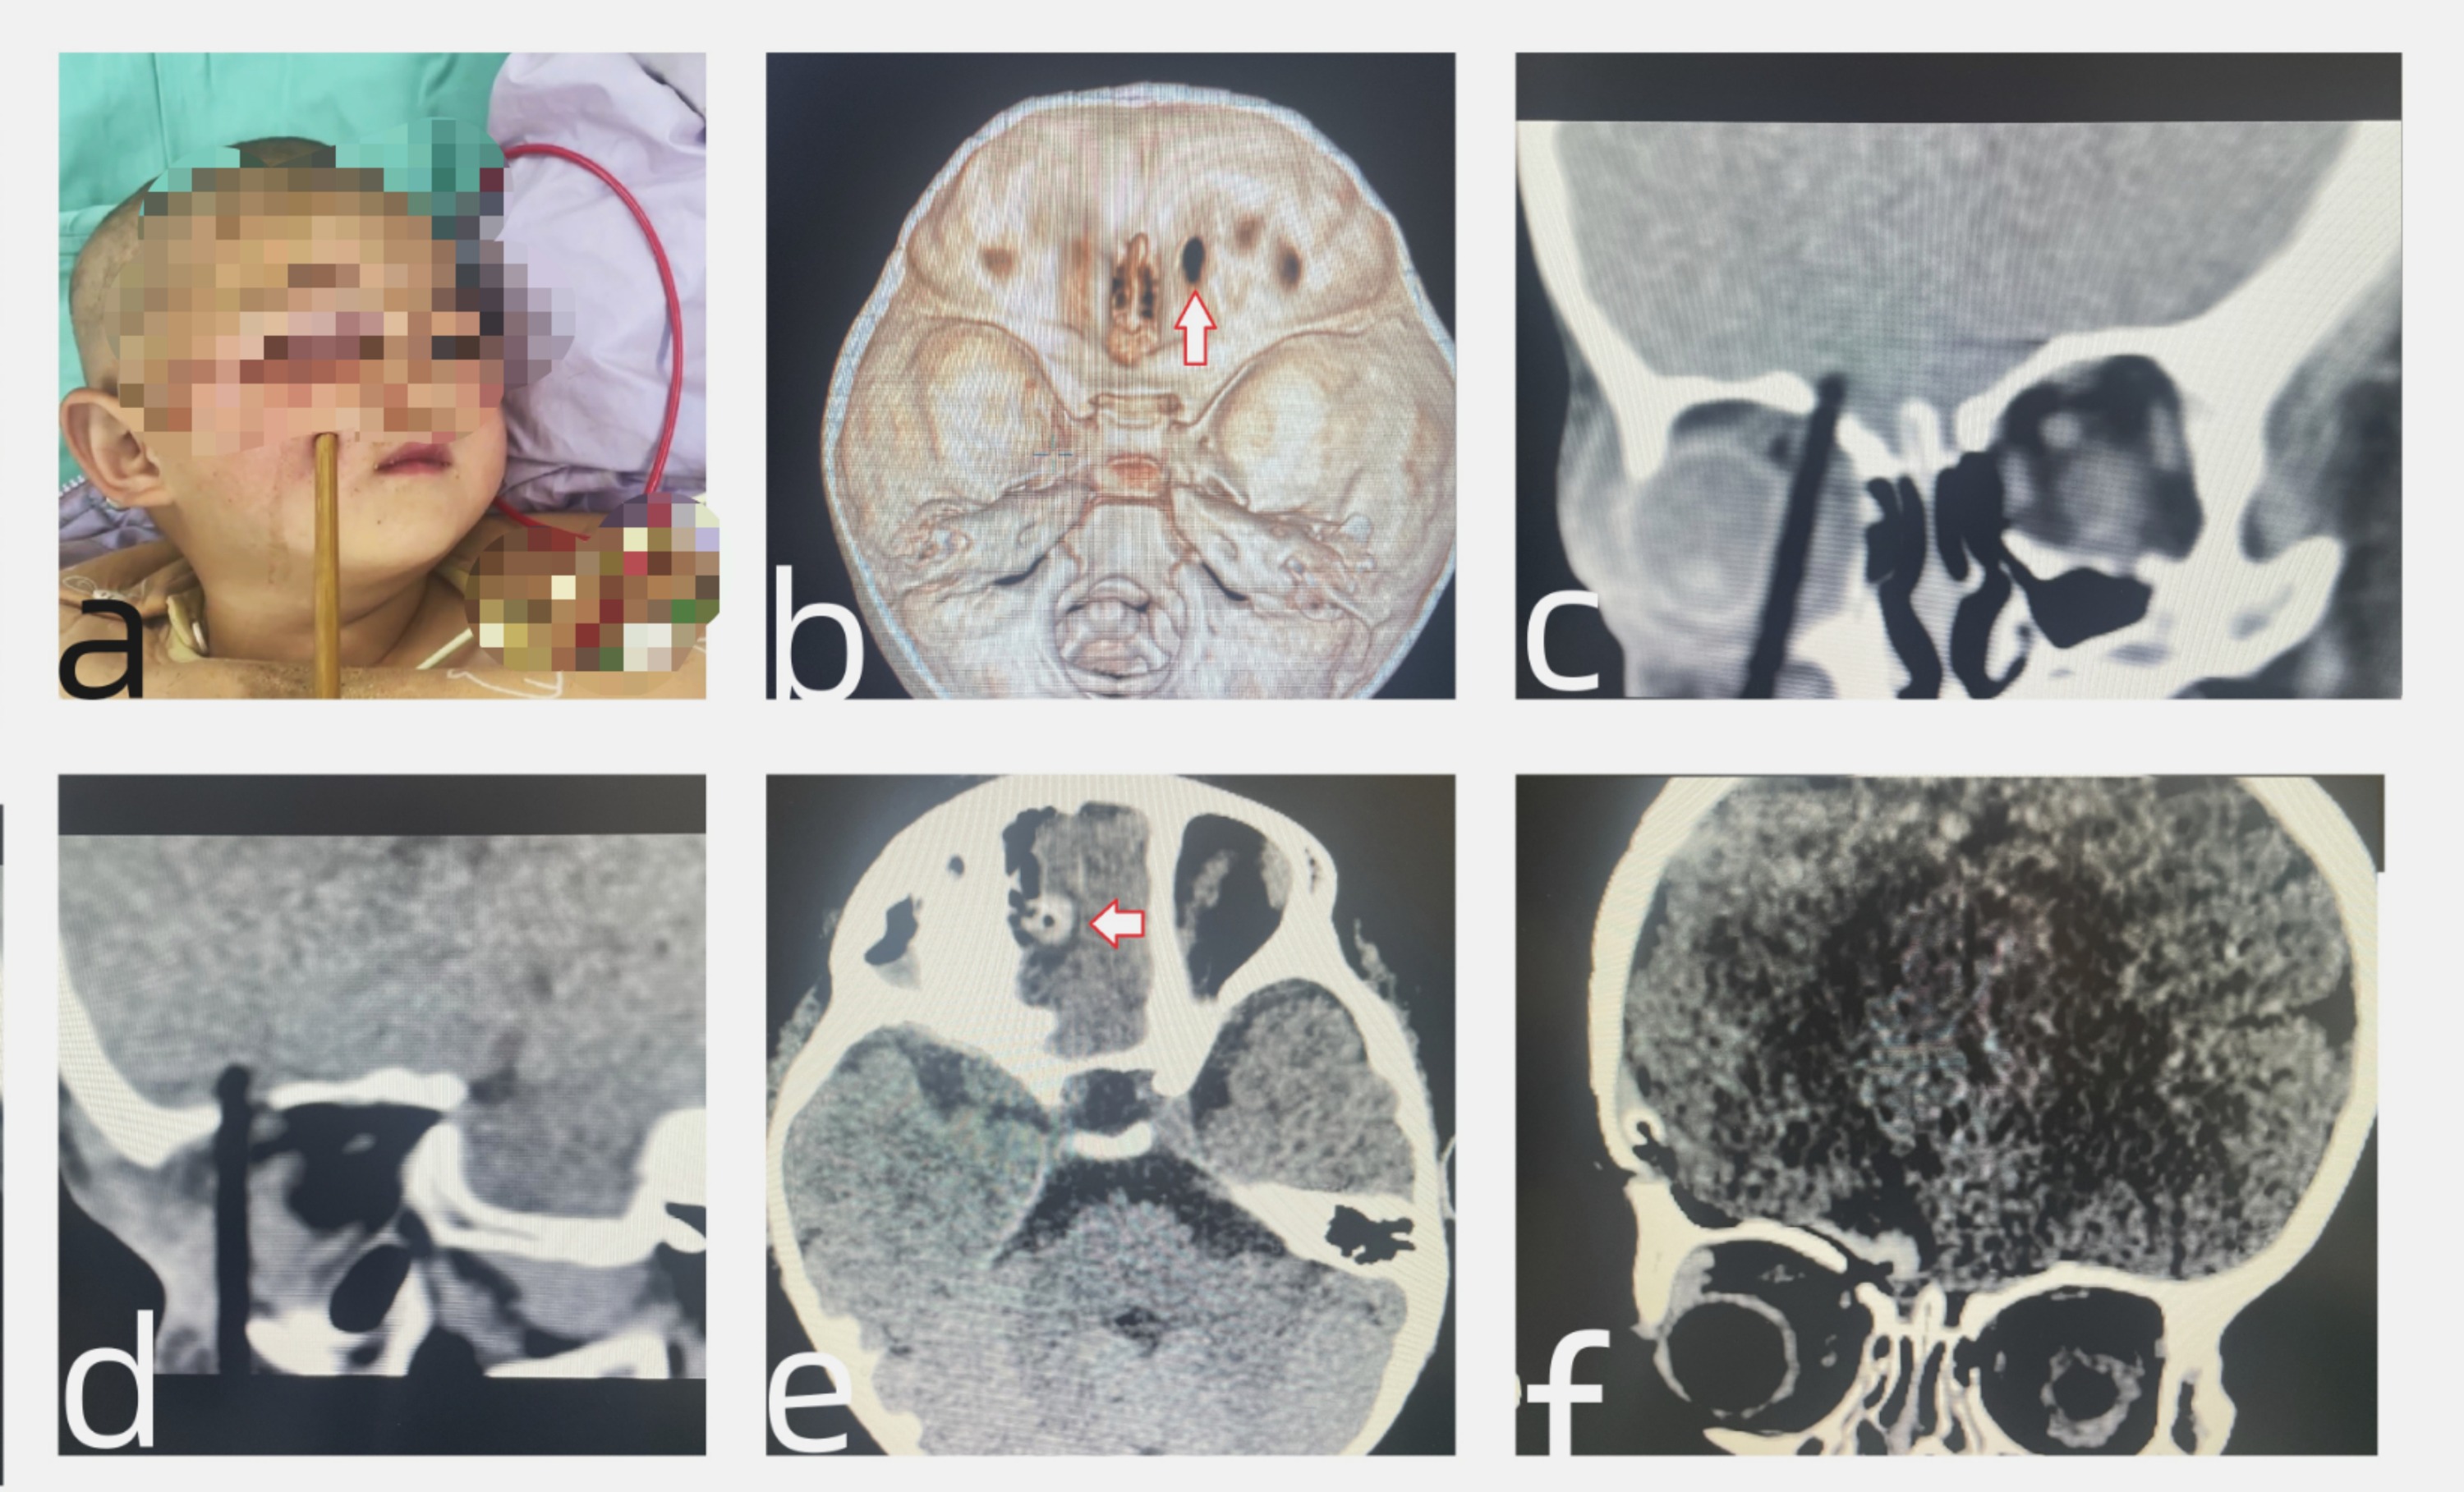

11月15日凌晨,上海儿童医学中心贵州医院儿童神经外科接诊并成功救治了一名不慎将筷子插入头部的2岁患儿。筷子贯穿患儿右侧面部并刺破前颅底插入脑内,儿童神经外科医生接诊后第一时间组织眼科、口腔颌面外科、儿童重症医学科、影像科、麻醉科等多学科力量会诊,迅速为患儿实施手术,成功化解了一场生命危机。

2岁患儿诺诺(化名)在吃饭时不慎摔倒,被筷子刺破右侧面颊,当即哭闹不止,右眼不能睁开,右侧眼睑及眶周肿胀、青紫,诺诺父母立即将孩子送往当地医院。颅脑显示,筷子竟已刺破诺诺的前颅底插入脑内。当地医生建议孩子到上级医院治疗,诺诺一家连夜赶往上海儿童医学中心贵州医院。

儿童神经外科专业组接诊后,根据患儿的情况在第一时间组织多学科会诊协作,成功为患儿进行了神经内镜联合显微镜下颅内碎骨片及异物取出,眶顶及硬脑膜缺损的修补术,颜面部裂伤的清创缝合术。

手术顺利完成,全程耗时约3个小时。术后患儿转入儿童重症医学科行重症监护和生命支持。1天后,患儿病情平稳,无神经功能缺损,复查CT后顺利转入儿童神经外科普通病房。

术前CT见筷子紧贴右侧眼球刺入脑内,术后CT复查前颅底重建满意